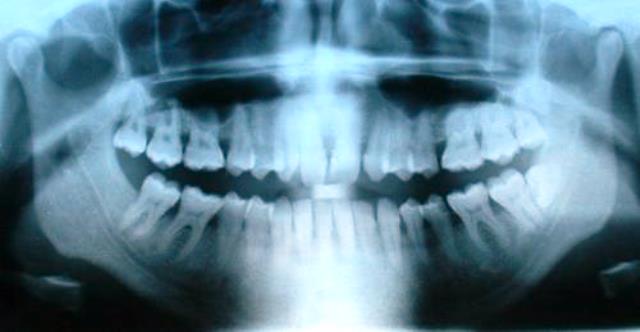

Зуб расположен в альвеолярном отростке верхней челюсти или в альвеолярной части нижней, состоит из ряда твёрдых тканей (такие, как зубная эмаль, дентин, зубной цемент) и мягких тканей (пульпа зуба). Анатомически различают коронку зуба (выступающую над десной часть зуба), корень зуба (часть зуба, расположенная глубоко в альвеоле, покрытая десной) и шейка зуба — различают клиническую и анатомическую шейки: клиническая соответствует краю десны, а анатомическая является местом перехода эмали в цемент, что означает, что анатомическая шейка является фактическим местом перехода коронки в корень. Примечательно, что клиническая шейка с возрастом смещается в сторону верхушки корня (апекса) (так как с возрастом происходит атрофия десны), а анатомическая — в противоположную (так как с возрастом эмаль истончается, а в области шейки может полностью истираться в силу того, что в области шейки её толщина гораздо меньше). Внутри зуба располагается полость, которая состоит из так называемых пульповой камеры и корневого канала зуба. Через специальное (апикальное) отверстие, расположенное в верхушке корня, в зуб идут артерии, которые доставляют все необходимые вещества, вены, лимфатические сосуды, обеспечивающие отток лишней жидкости и участвующие в механизмах местной защиты, а также нервы, осуществляющие иннервацию зуба.

Зубы (лат. dentes) — органы, которые размещены в альвеолярных отростках верхней и нижней челюсти и выполняют функцию первичной механической обработки еды. Челюсти взрослого человека содержат 32 постоянных зуба. По своему строению ткани зубов близкие к костной ткани, главные структурно-функциональные компоненты зуба являются производными соединительной ткани.

В каждом зубе различают коронку зуба (corona dentis), которая свободно выступает в ротовую полость , укрытую деснами шейку зуба и закрепленный в костной ткани альвеол корень зуба (radix dentis), который заканчивается верхушкой (apex radicis dentis).

Зуб построен из трёх шаров кальцификованных тканей: эмали, дентина и цемента. Полость зуба заполнена пульпой. Пульпа окружена дентином — основной кальцификованной тканью. На выступающей части зуба дентин покрыт эмалью. Погружённые в челюсть корни зубов покрыты цементом.